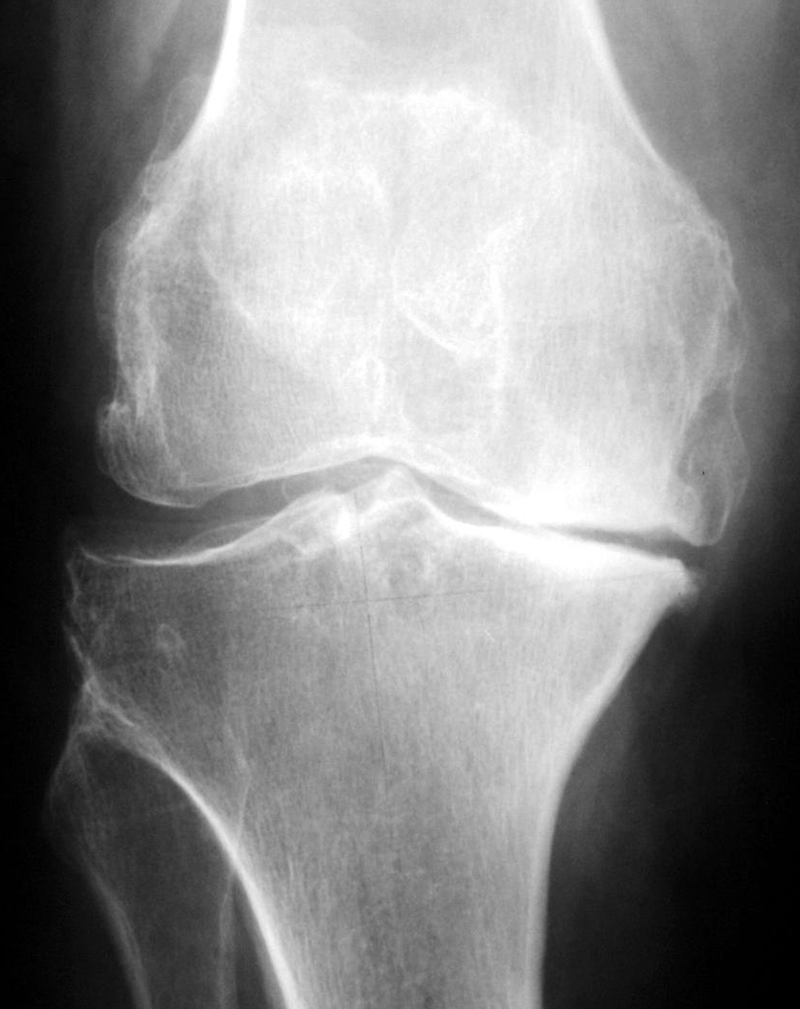

RÖNTGEN – verschlissenes Kniegelenk (groß)

Verschleiß